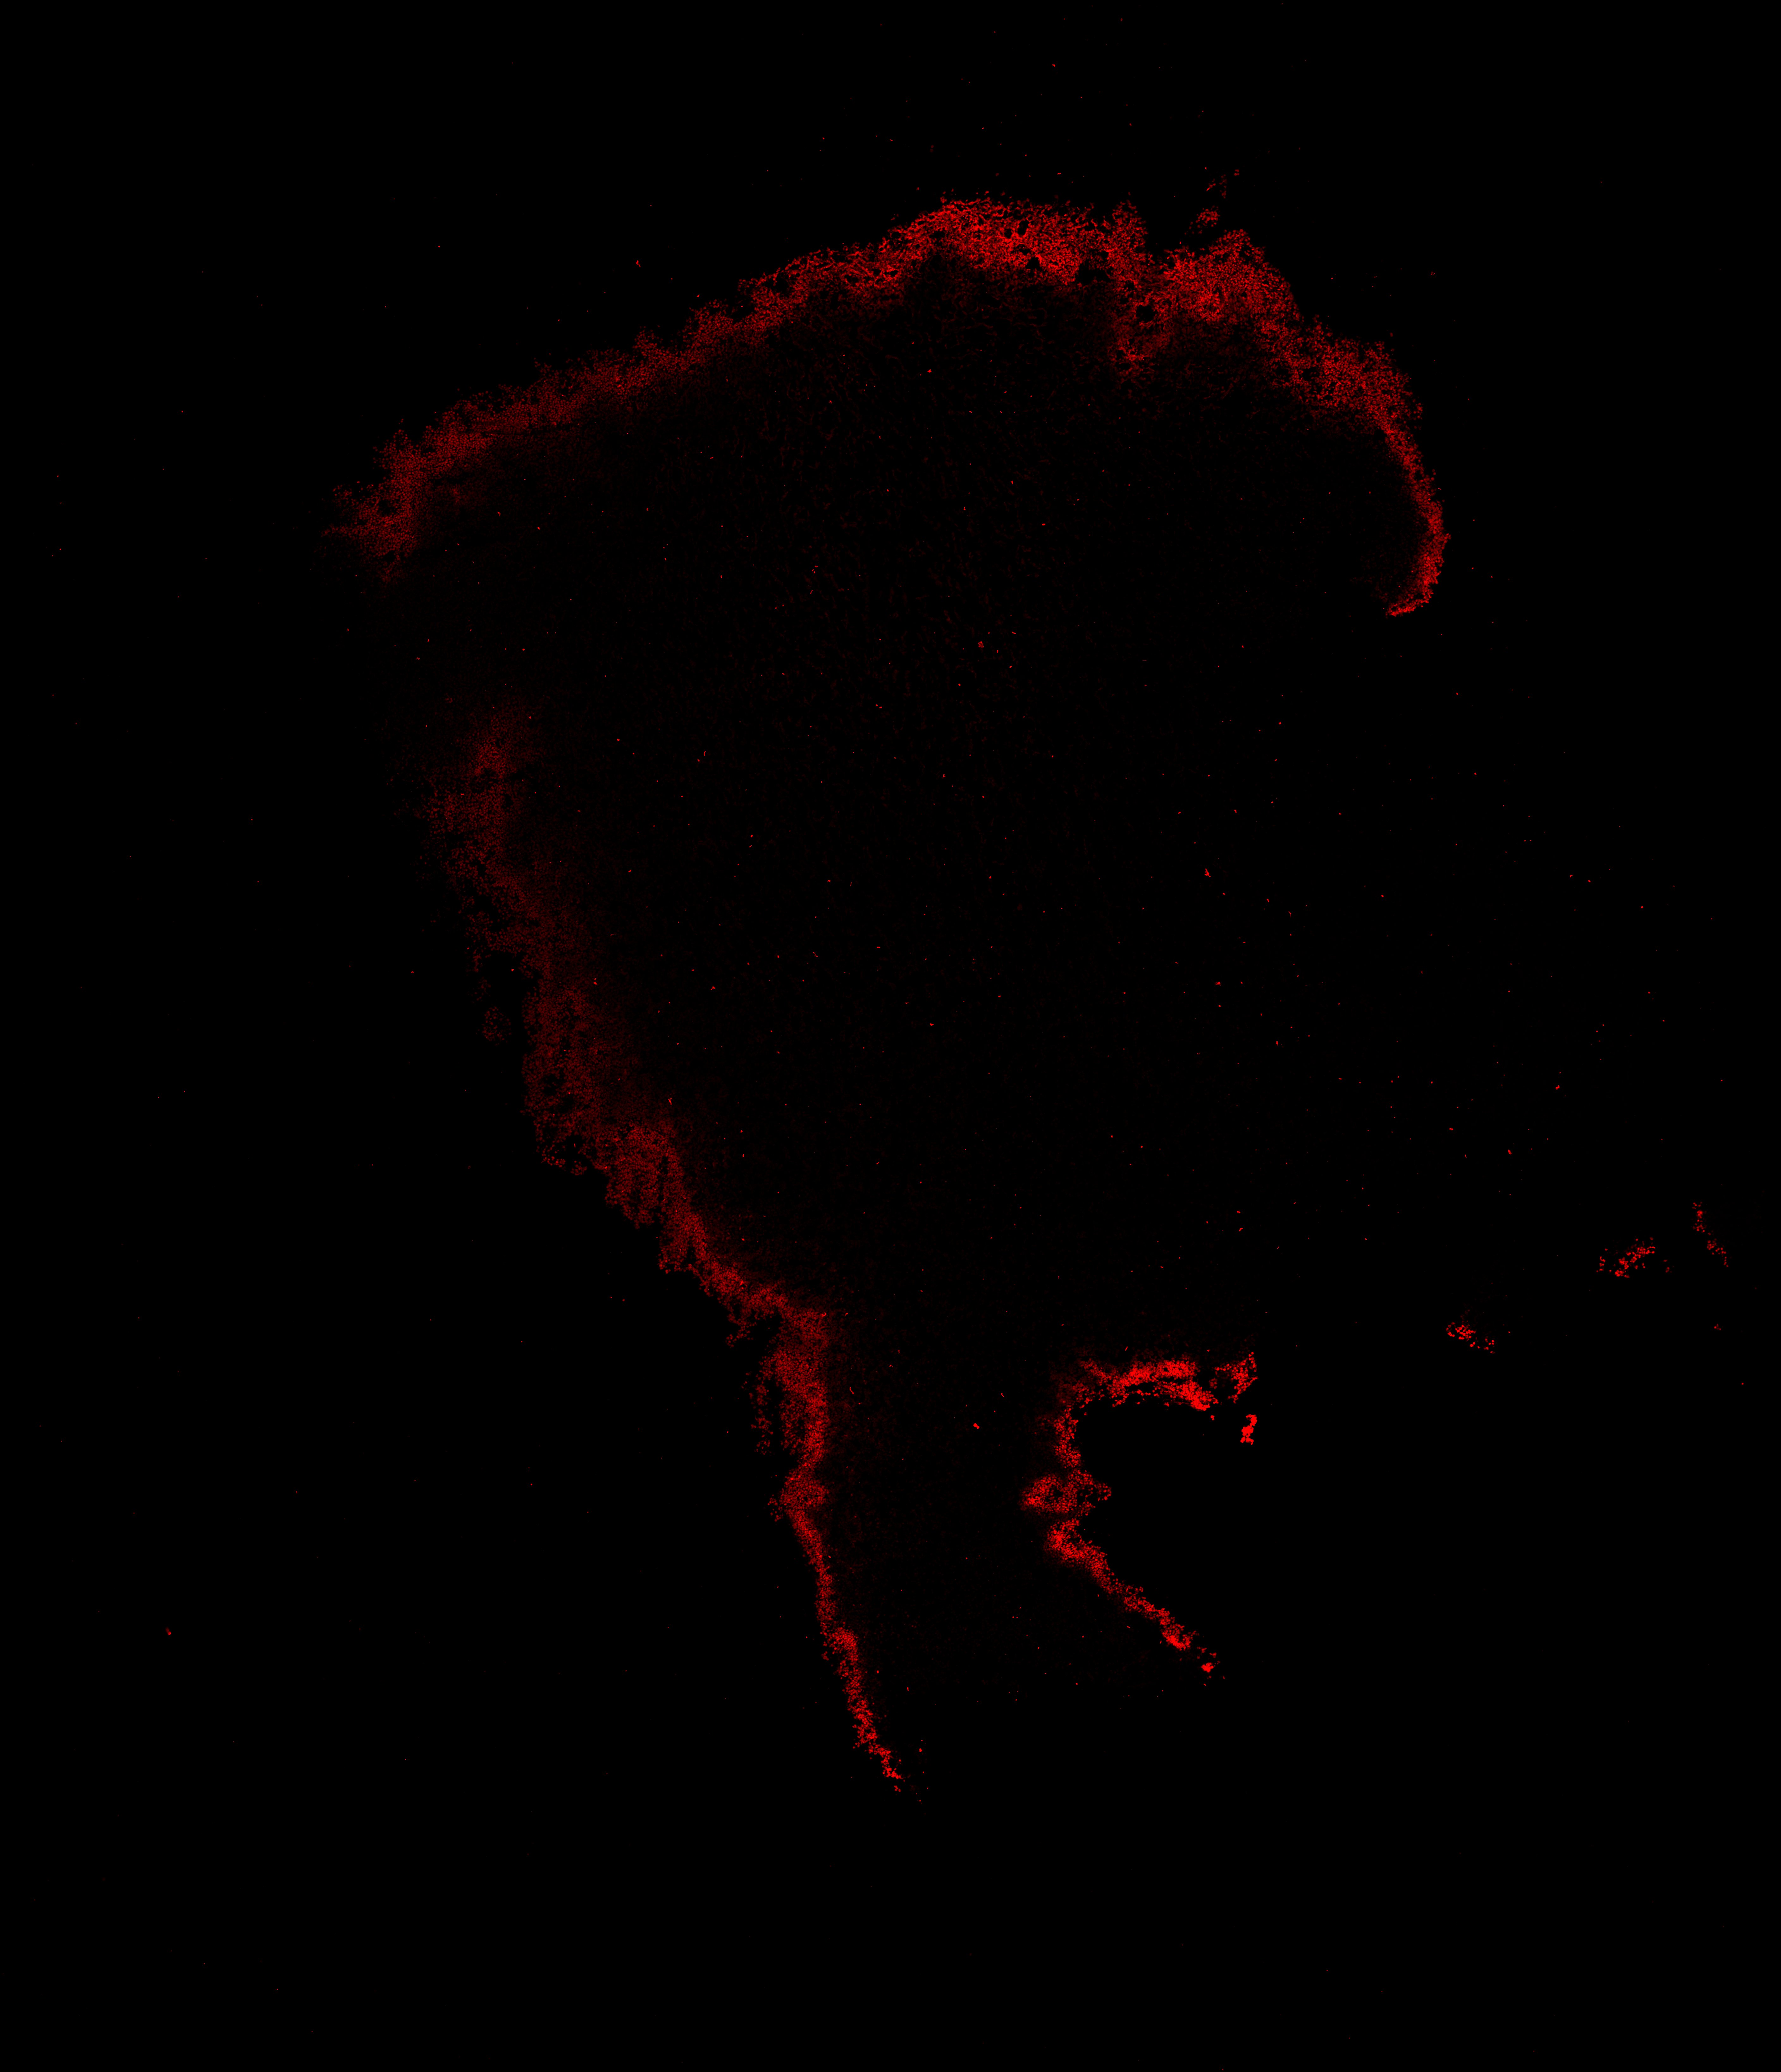

An anatomical analysis of the developing human midbrain from 6 post-conceptional weeks (PCW) to 22 PCW reveals increased tissue complexity, characterized by the emergence of dopaminergic nuclei, as highlighted by immunofluorescence analysis for tyrosine hydroxylase (TH).

17PCW

DAPI

17PCW human midbrain

MAP2

TH

Merged